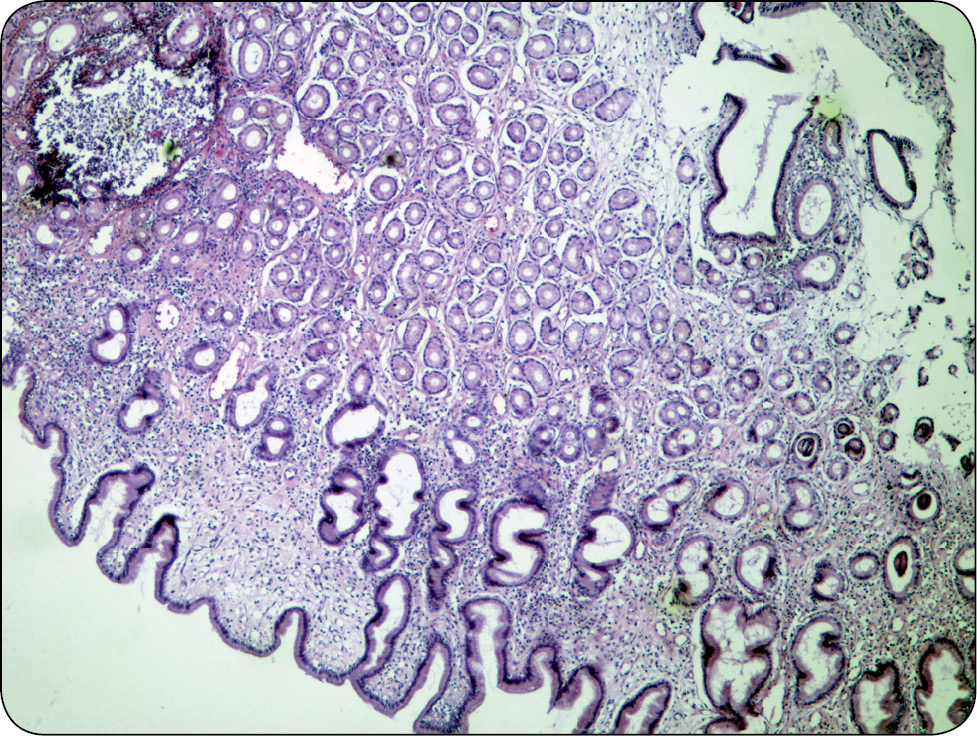

W badaniu histopatologicznym wycinków błony śluzowej żołądka rozpoznano przewlekłą gastropatię przerostową żołądka (ang. chronic giant hypertrophic gastropathy), obejmującą hipertrofię i hiperplazję błony śluzowej z towarzyszącym aktywnym przewlekłym procesem zapalnym o dużym nasileniu bez zmian nowotworowych (gastritis chronica magni gradus sine neoplasmate) – klasyfikacja Sydney: aktywność (+++), intensywność (+++), zanik gruczołowy (-), metaplazja jelitowa (-) (ryc. 3 i 4).